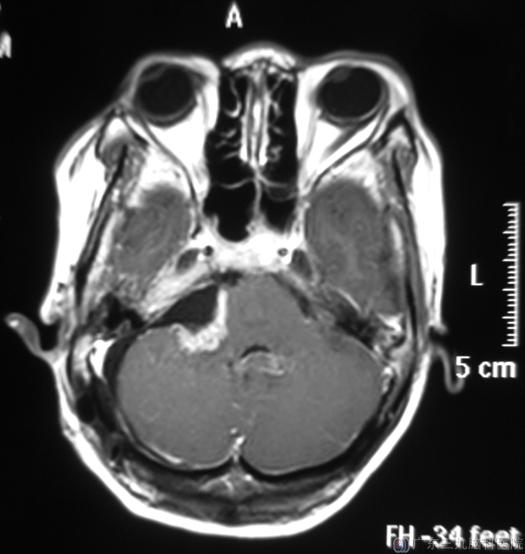

广东三九脑科医院综合神经外科 鲁明主任在切除听神经瘤时发现:肿瘤位于右侧桥小脑角区,质软,血供丰富,面神经位于肿瘤前下方,副神经、迷走神经、舌咽神经位于肿瘤后下方。在显微镜下用超声刀分块切除,磨钻磨除部分内听道,切除内听道内肿瘤组织,中后组颅神经保护完好。术后病理结果:(右侧桥小脑角)神经鞘瘤。

术后,黎姐的耳鸣症状已完全消失。

手术后